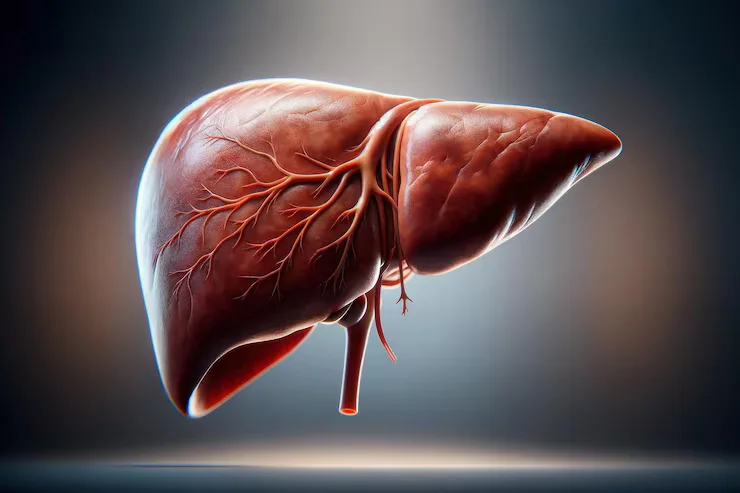

For Fatty Liver/ Liver Cirrhosis

Fatty Liver / Liver Cirrhosis Diet in Bangalore | Dr. Vinay Gastro Surgeon

Expert Care for Fatty Liver & Liver Cirrhosis with Diet and Lifestyle Management

Are you dealing with liver conditions such as fatty liver disease or liver cirrhosis, and looking for a dietary plan to support liver health?

At Dr. Vinay Gastro Surgeon Clinic, we specialize in providing dietary management for liver diseases, including fatty liver disease (NAFLD) and liver cirrhosis. Both conditions can be managed effectively through dietary modifications, lifestyle changes, and medical treatment. A balanced, liver-friendly diet can help reduce inflammation, prevent further liver damage, and support liver function.

What is Fatty Liver Disease (NAFLD) and Liver Cirrhosis?

Fatty liver disease (NAFLD) occurs when fat accumulates in the liver cells, leading to inflammation. It is commonly associated with obesity, poor diet, and diabetes. If untreated, it can progress to non-alcoholic steatohepatitis (NASH), which can eventually lead to cirrhosis.

Liver cirrhosis is the result of long-term liver damage caused by conditions like viral hepatitis, alcohol abuse, or fatty liver disease. Cirrhosis occurs when the liver becomes scarred, reducing its ability to function properly.